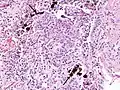

Micrograph of asbestosis showing the characteristic ferruginous bodies and marked interstitial fibrosis (or scarring). H&E stain.

Asbestosis resembles many other diffuse interstitial lung diseases, including other pneumoconiosis. The differential diagnosis includes idiopathic pulmonary fibrosis (IPF), hypersensitivity pneumonitis, sarcoidosis, and others. The presence of pleural plaques may provide supportive evidence of causation by asbestos. Although lung biopsy is usually not necessary, the presence of asbestos bodies in association with pulmonary fibrosis establishes the diagnosis.[26] Conversely, interstitial pulmonary fibrosis in the absence of asbestos bodies is most likely not asbestosis.[11] Asbestos bodies in the absence of fibrosis indicate exposure, not disease.